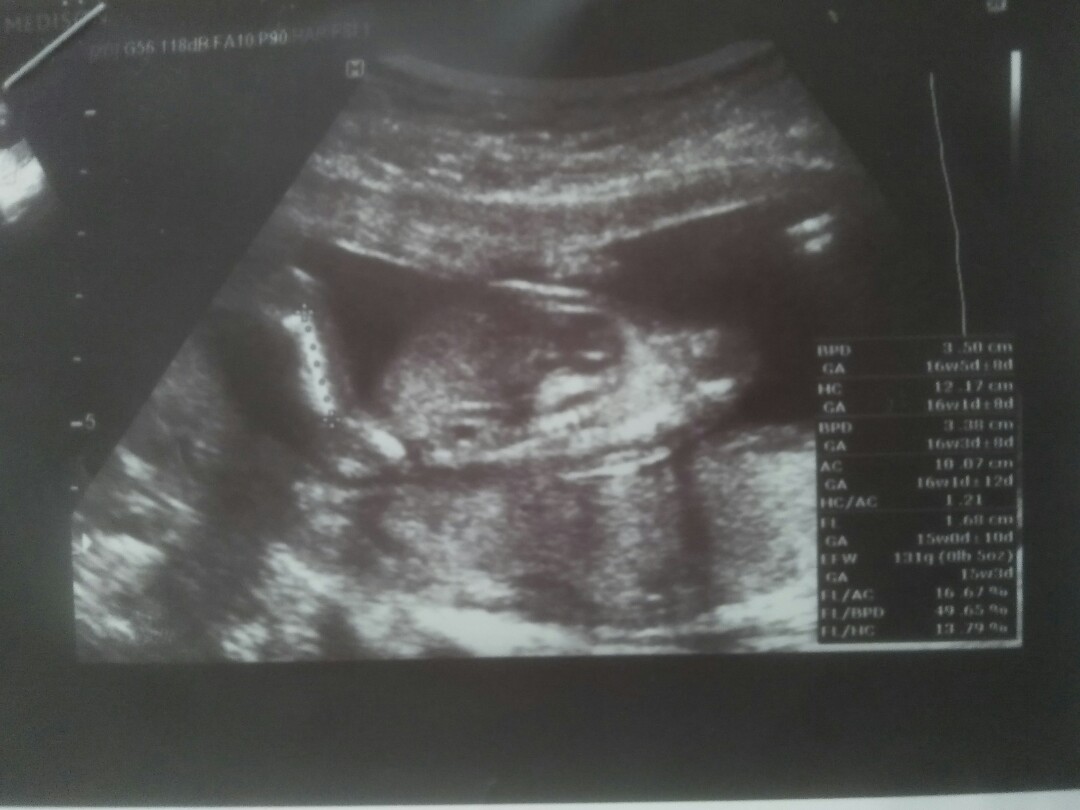

ใบซาวด์

ขอดูใบซาวด์เเม่ๆคลอดเดือนก.คหน่อยค่ะได้ผญหรือผชกันค่ะ

ผู้ชายค้า

ผู้ชายค่ะ